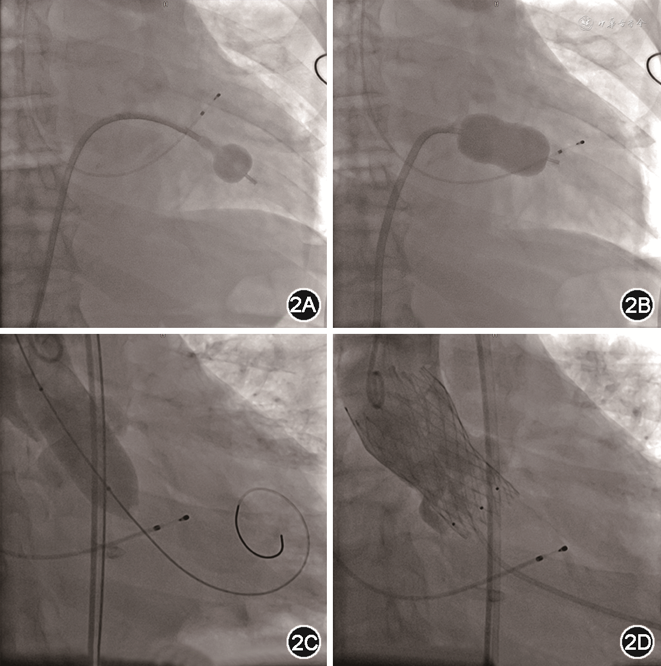

经与患者及其家属沟通后拟行经导管瓣膜手术。术中先行经皮二尖瓣球囊成形术(percutaneous balloon mitral valvuloplasty,PBMV),经右侧股静脉入路,选用24 mm Inoue球囊(日本Toray Industries Inc.)扩张二尖瓣。随后行TAVR,使用20 mm球囊预扩主动脉瓣后,植入26 mm VenusA人工主动脉瓣膜(杭州启明医疗),术后主动脉瓣最大跨瓣压差由80 mmHg降至3 mmHg(图2)。术后复查经胸超声心动图,结果示二尖瓣瓣口面积由0.8 cm2扩大至2.0 cm2,反流面积减少至4.9 cm2,主动脉瓣口血流速度降至1.62 m/s,峰值压差11 mmHg。NT-proBNP降至4 333 ng/L。